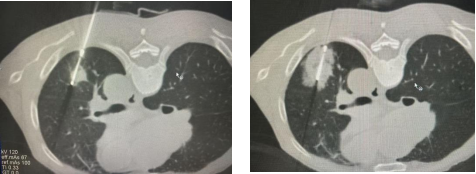

借助影像引导精准定位肿瘤,通过特制消融针将局部温度骤降至-140℃至-170℃,使肿瘤细胞迅速结晶坏死,并阻断周围血管营养供应;

随后温度快速回升至20-40℃,温差加重细胞损伤程度,达到治疗目的。

肺癌冷冻消融治疗的核心在于其超低温精准打击能力。通过高精度的影像引导系统,医生能够准确锁定肿瘤位置,随后利用特制消融针将肿瘤组织迅速冷冻至极低温状态,这一温度几乎可以瞬间“冻结”肿瘤细胞,使其失去活性并逐步死亡。相比传统疗法,冷冻消融的精准度更高,能有效减少对健康组织的损伤,实现“点对点”的精准治疗。